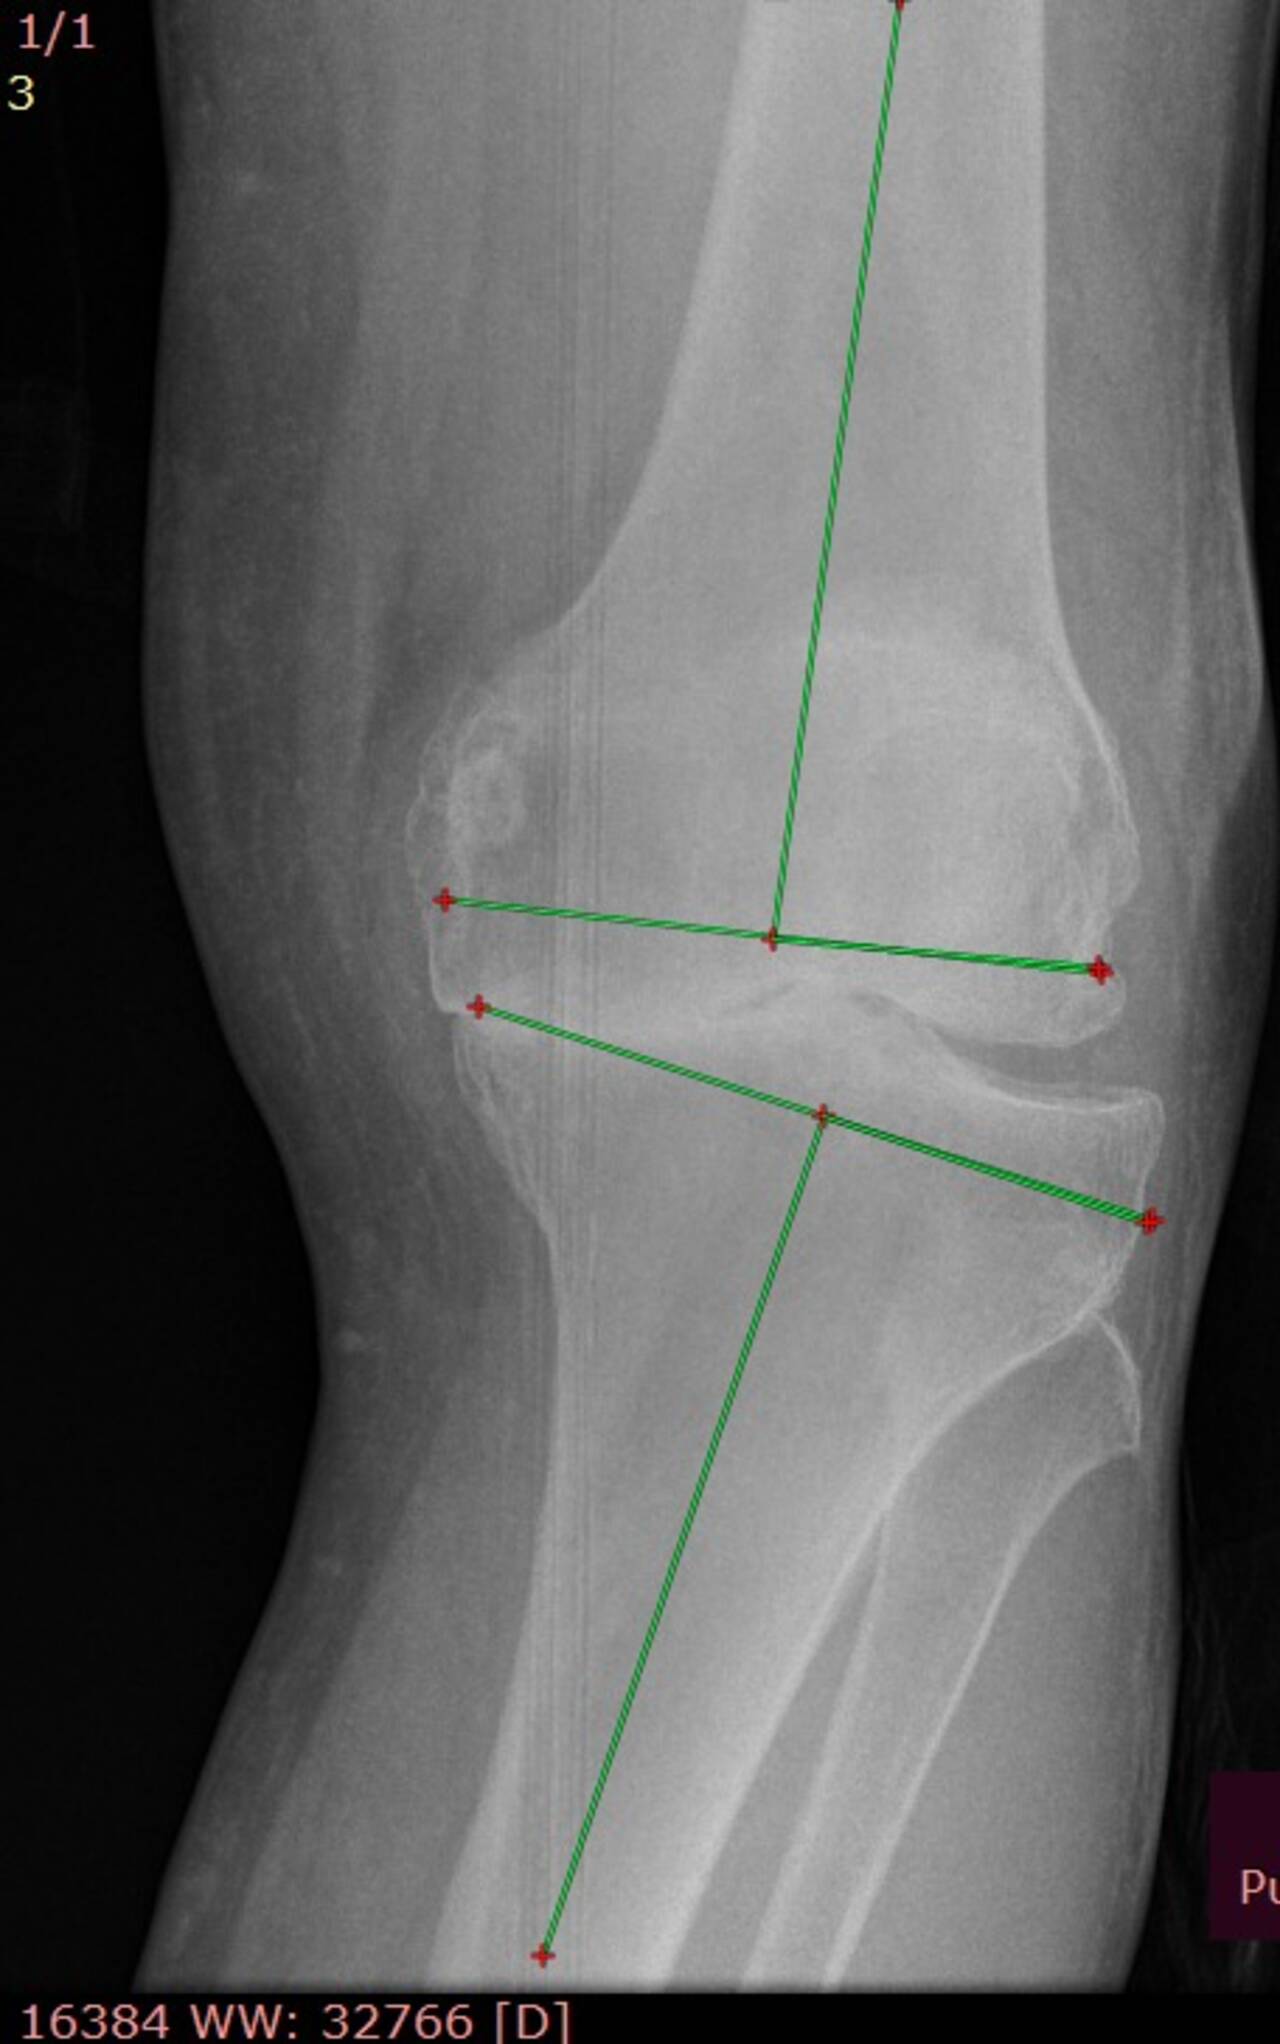

La satisfacción y el bienestar de nuestros pacientes son la mejor prueba del éxito de cada tratamiento. A través de testimonios reales y casos de éxito, compartimos historias de quienes han recuperado por completo la funcionalidad de sus rodillas y han vuelto a sus actividades diarias sin dolor ni limitaciones.

Cada paciente es un testimonio de compromiso, excelencia médica y el impacto positivo de los tratamientos personalizados en artroscopia y reconstrucción articular. ¡Descubre cómo un enfoque especializado puede transformar vidas!